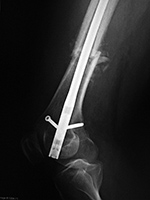

Left knee antegrade intramedullary rod displacement into knee joint |